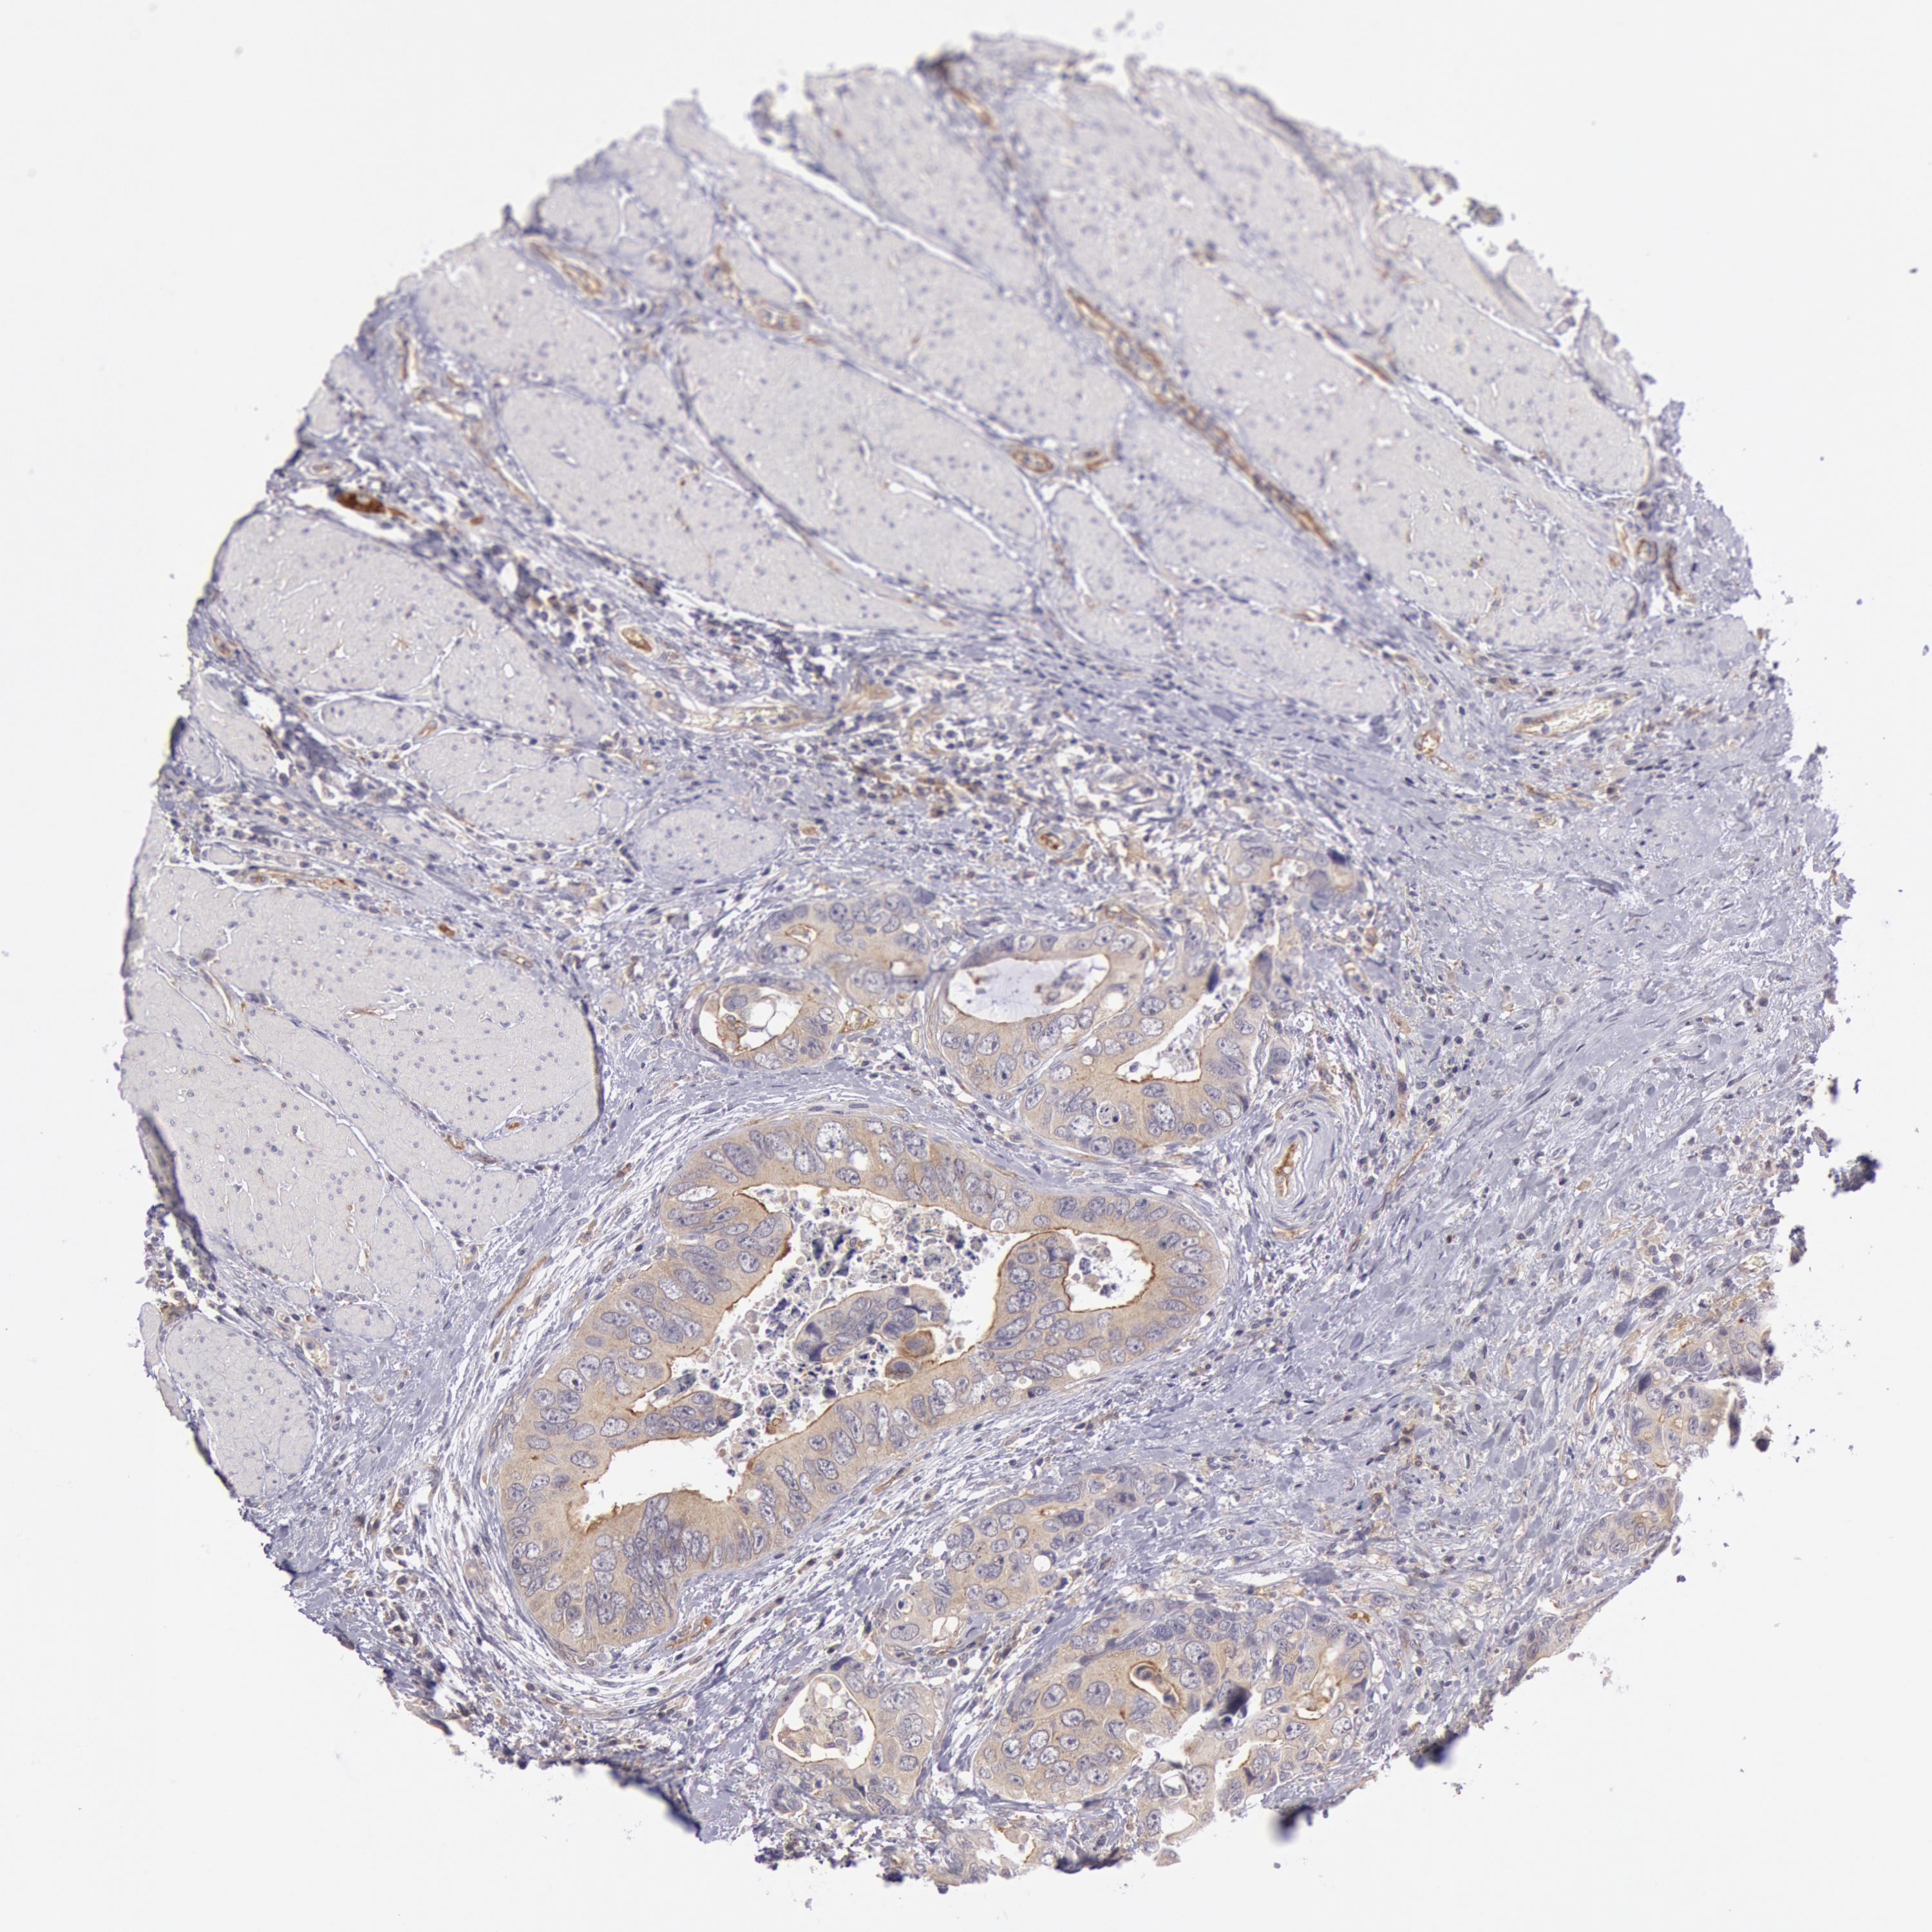

CANCER COLORECTAL CANCER Show tissue menu

Colorectal cancer

Human cancer

Colon adenocarcinoma